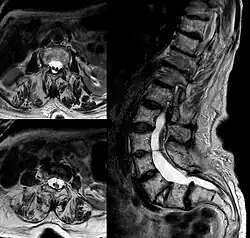

Rozdwojenie rdzenia kręgowego (łac. diastematomyelia, ang. diastematomyelia) – wada wrodzona z grupy dysrafii, polegająca na podziale rdzenia kręgowego na symetryczne połowy wzdłuż jego osi długiej. Połowy rdzenia znajdują się w pojedynczym lub w oddzielnych workach opony twardej. Podział zwykle jest dokonany na odcinku lędźwiowym, rzadziej na odcinku piersiowym rdzenia. Między połowami podzielonego rdzenia znajduje się przegroda kostna lub łącznotkankowa. Wada może być bezobjawowa, niekiedy obecne są jednak objawy ogniskowe. Zbliżoną wadą jest zdwojenie rdzenia (diplomyelia), polegające na obecności dwóch oddzielnych rdzeni.